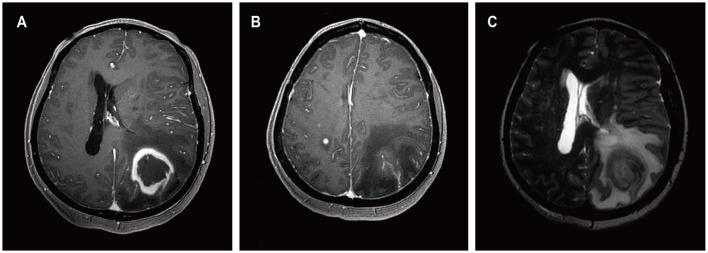

Four patients had previously received a kidney transplant, one had undergone allogeneic HSCT. The median time from the last transplant surgery to the diagnosis of PCNS-PTLD differs between kidney transplant (21.5 years) and allogeneic HSCT (9 months). Common symptoms included motor weakness ( = 4), headache ( = 2), confusion ( = 2), and nausea ( = 2), with ring-enhancing ( = 5), typically solitary ( = 3) and supratentorial ( = 3) lesions on imaging. Diagnosis involved robot-assisted stereotactic brain biopsy ( = 4) or craniotomy ( = 1), all showing Epstein-Barr virus and CD20 positivity. Most cases ( = 4) were monomorphic diffuse large B-cell lymphoma. Treatment included rituximab ( = 3), surgical resection ( = 2), zanubrutinib ( = 1), whole-brain radiation ( = 1), and methotrexate ( = 1). At the last follow-up, the median duration of follow-up for all patients was 19 months. During this time, 3 patients had died and 2 patients were still alive.

In patients with a history of kidney transplantation or allogeneic HSCT who are on long-term immunosuppressive therapy, any neurological symptoms, particularly the presence of supratentorial ring-enhancing masses in the brain on imaging, whether solitary or multiple, should raise high suspicion for this disease, warranting a timely brain biopsy. Additionally, we found that besides reducing immunosuppressants, zanubrutinib may be a potential, safe, and effective treatment for this condition. Moreover, post-surgical administration of rituximab in conjunction with whole-brain radiotherapy also appears to be a potentially safe and effective approach.

4例患者曾接受肾移植,1例接受异基因HSCT。从最后一次移植手术到诊断为PCNS-PTLD的中位时间在肾移植(21.5年)和异基因HSCT(9个月)之间有所不同。常见症状包括运动无力(n = 4)、头痛(n = 2)、意识模糊(n = 2)和恶心(n = 2),影像学检查显示有环形强化(n = 5),通常为单发(n = 3)且位于幕上(n = 3)病变。诊断采用机器人辅助立体定向脑活检(n = 4)或开颅手术(n = 1),所有结果均显示爱泼斯坦-巴尔病毒和CD20阳性。大多数病例(n = 4)为单形性弥漫性大B细胞淋巴瘤。治疗方法包括利妥昔单抗(n = 3)、手术切除(n = 2)、泽布替尼(n = 1)、全脑放疗(n = 1)和甲氨蝶呤(n = 1)。在最后一次随访时,所有患者的中位随访时间为19个月。在此期间,3例患者死亡,2例患者仍存活。

对于有肾移植或异基因HSCT病史且长期接受免疫抑制治疗的患者,任何神经系统症状,特别是影像学检查显示脑内幕上有环形强化肿块,无论单发或多发,都应高度怀疑此病,需及时进行脑活检。此外,我们发现除了减少免疫抑制剂外,泽布替尼可能是治疗这种疾病的一种潜在、安全且有效的方法。此外,术后给予利妥昔单抗联合全脑放疗似乎也是一种潜在安全有效的方法。